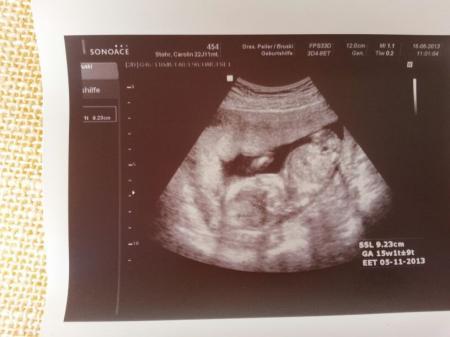

hallo ihr lieben . habe einen sehr ausgiebigen ultraschall gehabt ( klar bezahlt ) und nun wissen wir es wird sicher ein JUNGE .. oh man habe mir sooo ein mädchen gewünscht aber was solls . war einfach glücklich das alles dranist und kern gesund :) und sooo süß hat mit seinen beinen gespielt . mit seinen händen festgehalten so süß und total am zappeln . ist kanpp 10 cm groß

Bild zu so auch wieder da mit outing - Forum für November - Mamis